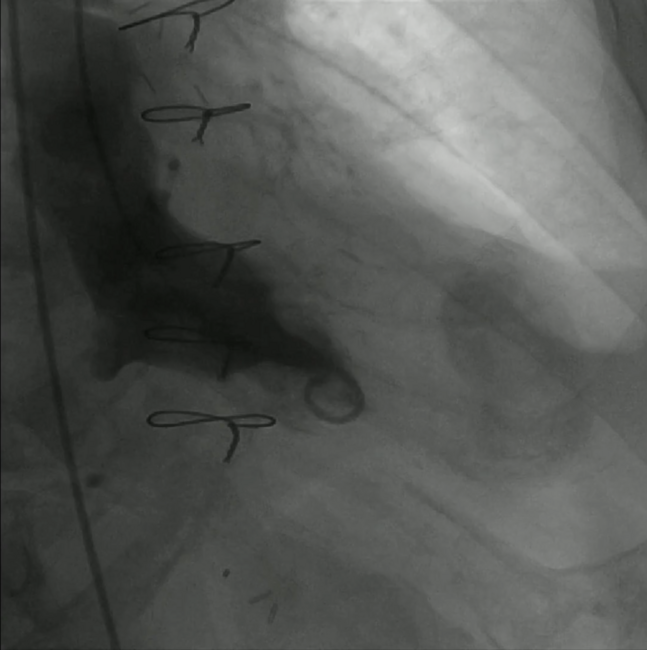

An 80-year-old patient with type A aortic dissection underwent emergent supracoronary ascending aorta and hemi-arch replacement surgery followed by aortic valve and partial root replacement during the same admission due to complications. Three months later, he was readmitted with heart failure symptoms. Transthoracic echocardiography(TTE) showed pericardial effusion and a large pseudoaneurysm with narrow neck at the left ventricular (LV) apex, which was partially thrombosed (Video 1). Due to unacceptably high surgical risk, a percutaneous closure was planned. Under TTE guidance, an 8 mm ventricular septal defect Amplatzer occluder device (St. Jude Medical) was successfully implanted in a retrograde fashion (Videos 2-4 and Figure 1). The TTE showed minimal residual leak (Video 5). Finally, percutaneous drainage of the pseudoaneurysm was performed.

LV pseudoaneurysm is a rare complication of myocardial infarction, interventional procedures, trauma, infection, or cardiac surgery. High rates of spontaneous rupture and death have been described when the pseudoaneurysm is left untreated. Percutaneous closure has emerged as an alternative to surgery in patients with unacceptable surgical risk. In this case, TTE allowed optimal characterization of the defect and successful procedure guidance, avoiding risks derived from more invasive intraprocedural imaging techniques.